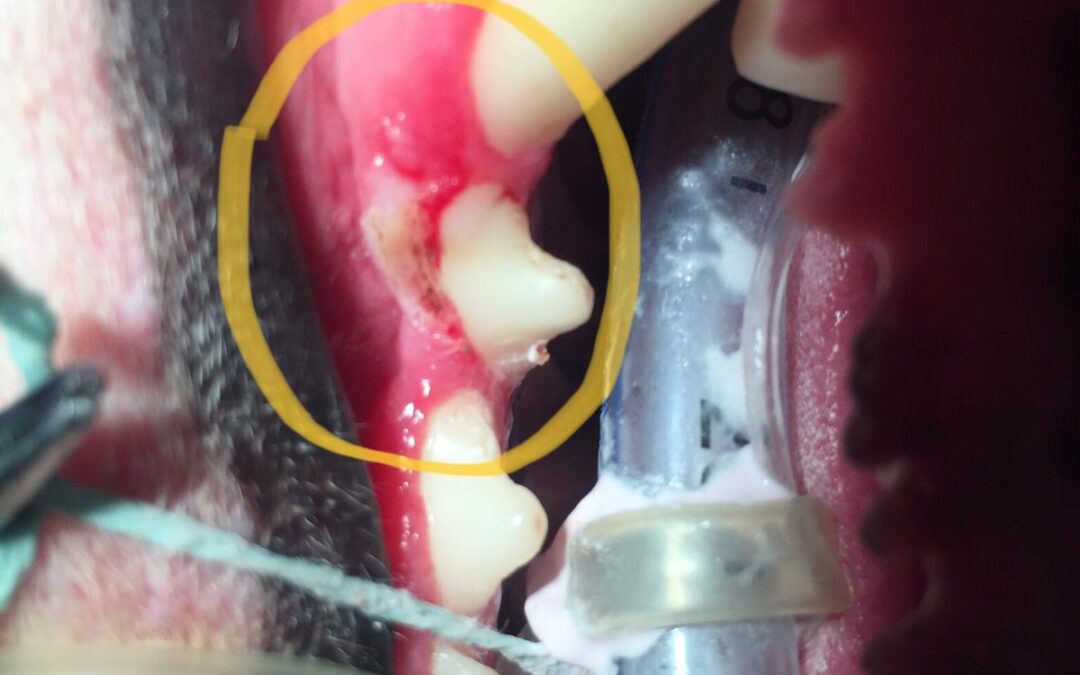

tazz post mass